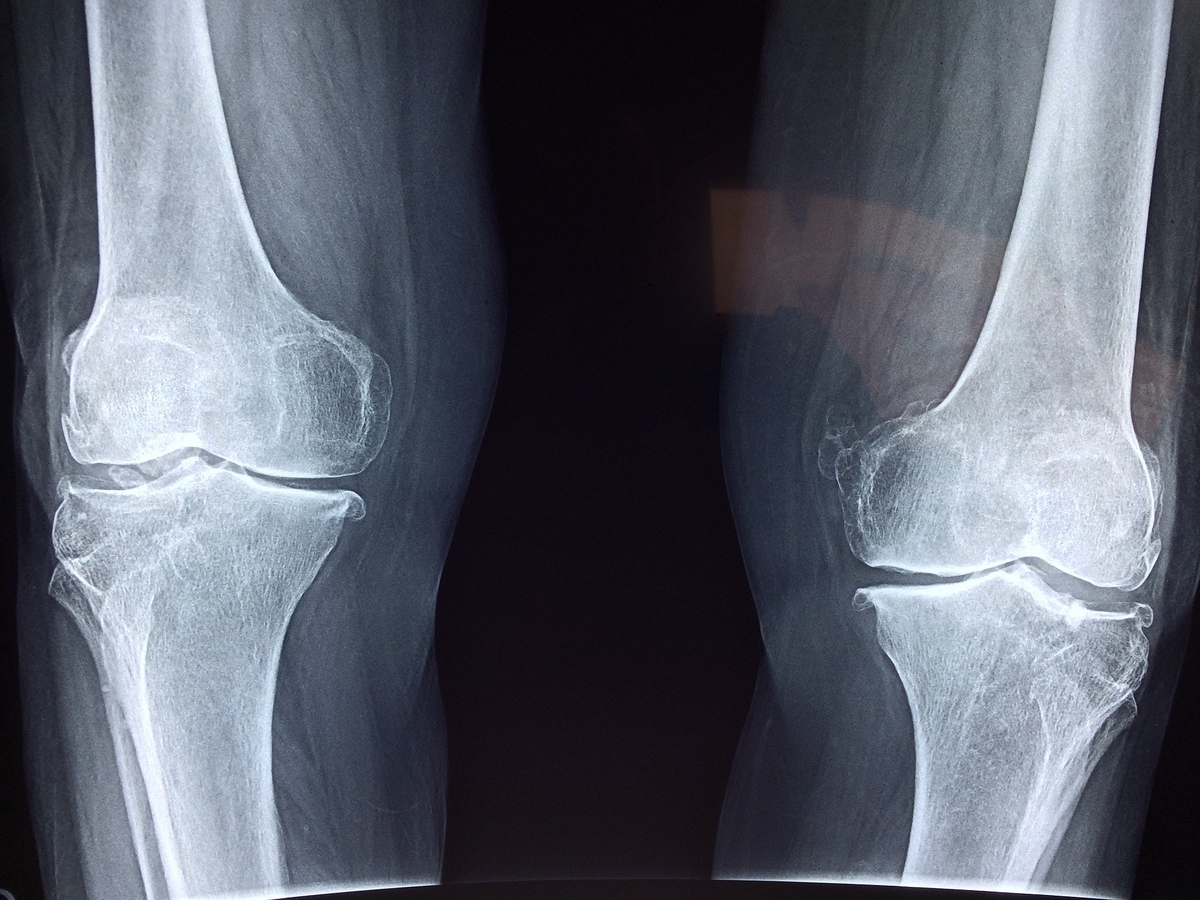

悪性骨腫瘍 日本整形外科学会 症状 病気をしらべる

原発性悪性骨腫瘍 06 筋骨格疾患と結合組織疾患 Msdマニュアル プロフェッショナル版

原発性悪性骨腫瘍 08 骨 関節 筋肉の病気 Msdマニュアル家庭版